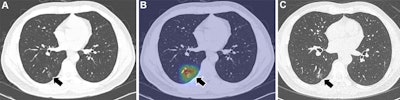

Examples of Sybil, an open-source deep learning model, correctly predicting lung cancers (visible lung cancer at baseline CT). (A) Axial low-dose CT image of the lungs in a 54-year-old heavy-smoking man shows a 1.5-cm subsolid nodule in the right lower lobe, with the (B) attention map focusing on this area (arrow). The Sybil lung risk scores were 13.1% for 1-year risk, 20.2% for 2-year risk, 20.7% for 3-year risk, 23.6% for 4-year risk, 24.8% for 5-year risk, and 31.2% for 6-year risk. (C) Axial CT image after two years shows that the subsolid nodule had grown to 2 cm and was subsequently diagnosed as adenocarcinoma (arrow). The Sybil lung risk score is a deep learning-based risk score for predicting future lung cancer risk within 6 years from a low-dose chest CT scan.Examples of Sybil, an open-source deep learning model, correctly predicting lung cancers (visible lung cancer at baseline CT). (A) Axial low-dose CT image of the lungs in a 54-year-old heavy-smoking man shows a 1.5-cm subsolid nodule in the right lower lobe, with the (B) attention map focusing on this area (arrow). The Sybil lung risk scores were 13.1% for 1-year risk, 20.2% for 2-year risk, 20.7% for 3-year risk, 23.6% for 4-year risk, 24.8% for 5-year risk, and 31.2% for 6-year risk. (C) Axial CT image after two years shows that the subsolid nodule had grown to 2 cm and was subsequently diagnosed as adenocarcinoma (arrow). The Sybil lung risk score is a deep learning-based risk score for predicting future lung cancer risk within 6 years from a low-dose chest CT scan.Radiology and Jong Hyuk Lee, MD, PhD.